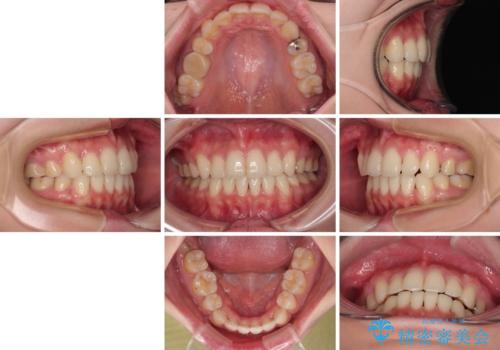

- 八重歯やクロスバイトを気にして来院された患者様です。

口元の突出感はありませんでしたが、デコボコが強く、非抜歯矯正とすると出っ歯仕上がりとなる可能性があったため、上下左右の第一小臼歯4本を抜歯し、ワイヤー装置にて矯正治療を行うこととしました。

デコボコがスッキリするだけでなく、口元の突出感も少し改善され、満足のいく仕上がりとなりました。